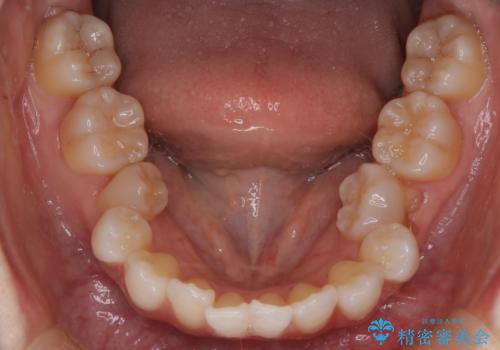

ハーフリンガル矯正|上下4本の抜歯で叢生を改善し、美しい歯並びへ

- 患者様は、歯並びの乱れ(叢生)を整えたいが、前歯の突出感は気にならないとのことで来院されました。診察の結果、全体的な歯列のスペース不足により抜歯が必要と判断。しかし、前歯を大きく下げる必要はなかったため、小臼歯の中でも5番(第二小臼歯)を抜歯する治療計画を立てました。装置は、上顎が舌側(リンガル)、下顎が表側(審美ワイヤー)のハーフリンガル矯正を採用し、目立ちにくさと効率的な歯の移動を両立しました。

抜歯によって歯を並べるためのスペースを確保。その後、ハーフリンガル矯正を用いて、上顎は舌側から、下顎は目立ちにくいワイヤーで歯を誘導し、歯列全体を整えました。治療期間を通じて、噛み合わせのバランスも改善し、機能的にも審美的にも理想的な仕上がりとなりました。患者様からは「目立たずに矯正でき、きれいな歯並びになって嬉しい」とご満足いただきました。